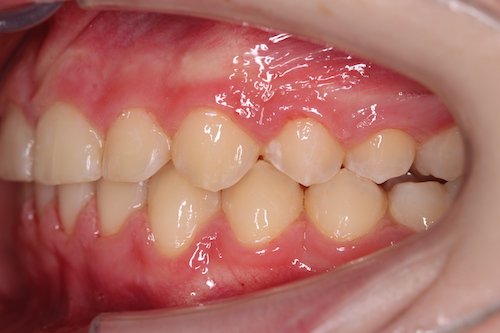

До